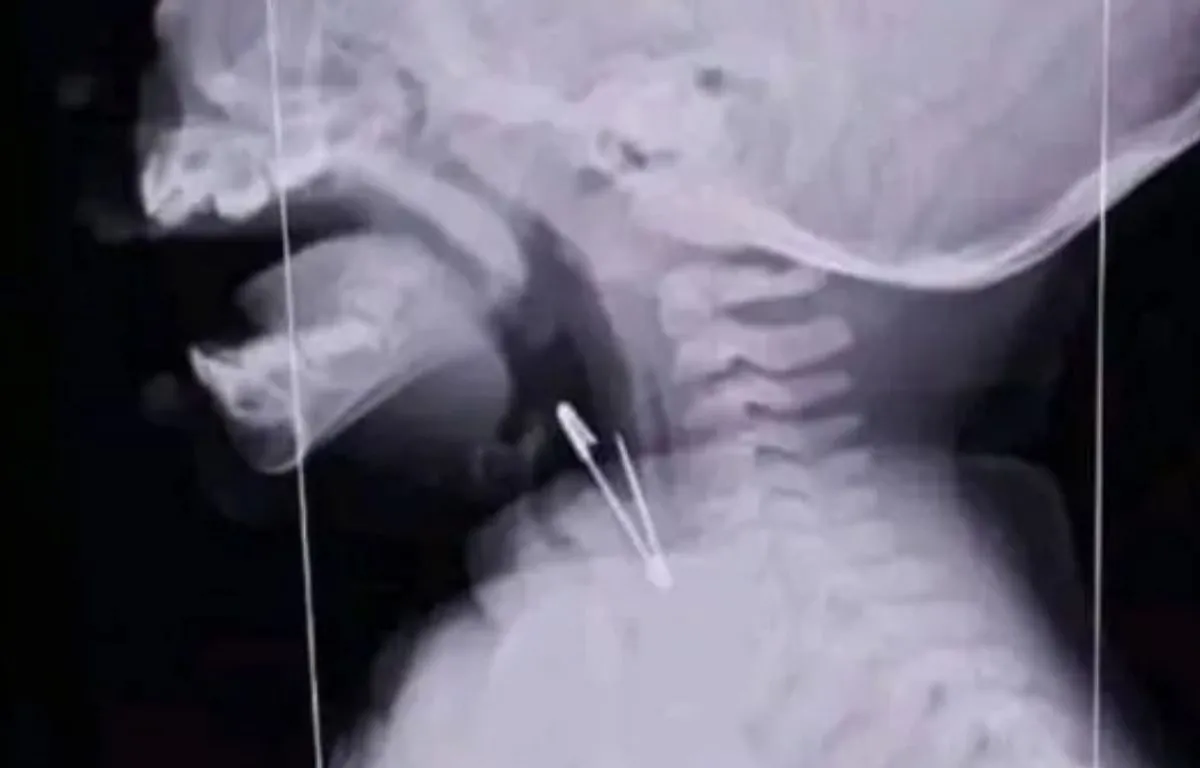

Como se ve en la radiografía a la cual accedieron los medios de comunicación, el objeto punzante se alojó en la zona de la laringe, lo que implicó un trabajo prácticamente artesanal para retirárselo sin poner en peligro su vida cuidando cada músculo de su garganta.